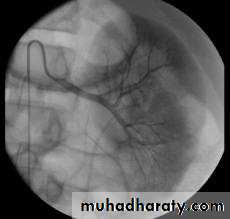

Angiogram or MRIA.

Indicated in:young patients with uncontrolled hypertension. ('resistant hypertension').

those who have a history of ‘recurrent ' pulmonary oedema .

accelerated phase ('malignant') hypertension.

those in whom renal function is deteriorating.

angioplasty, with placement of stents in atherosclerotic disease areas to improve primary patency rates and prevent rapid recurrence.

Angioplasty complication:

contrast nephropathy .

renal artery occlusion and renal infarction.

and atheroemboli from manipulations in a severely diseased aorta.